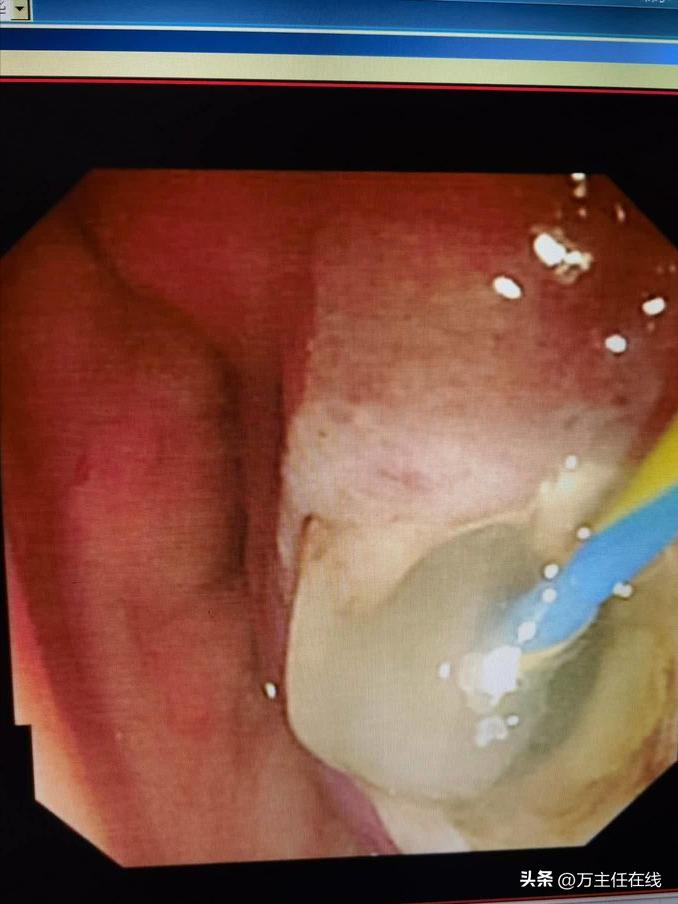

万主任手术中,水刀扩大切口

水刀扩大胃窦造瘘口,预防短期内闭合

水刀扩大胃窦造瘘口后,保持腹腔粘液通畅胃内引流